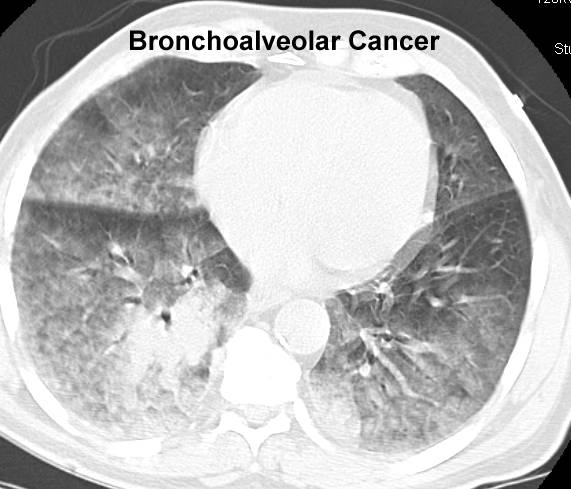

mediastinal mass, CT

large hilar mass, brochoalveolar #1, brochoalveolar #2, mesothelioma,